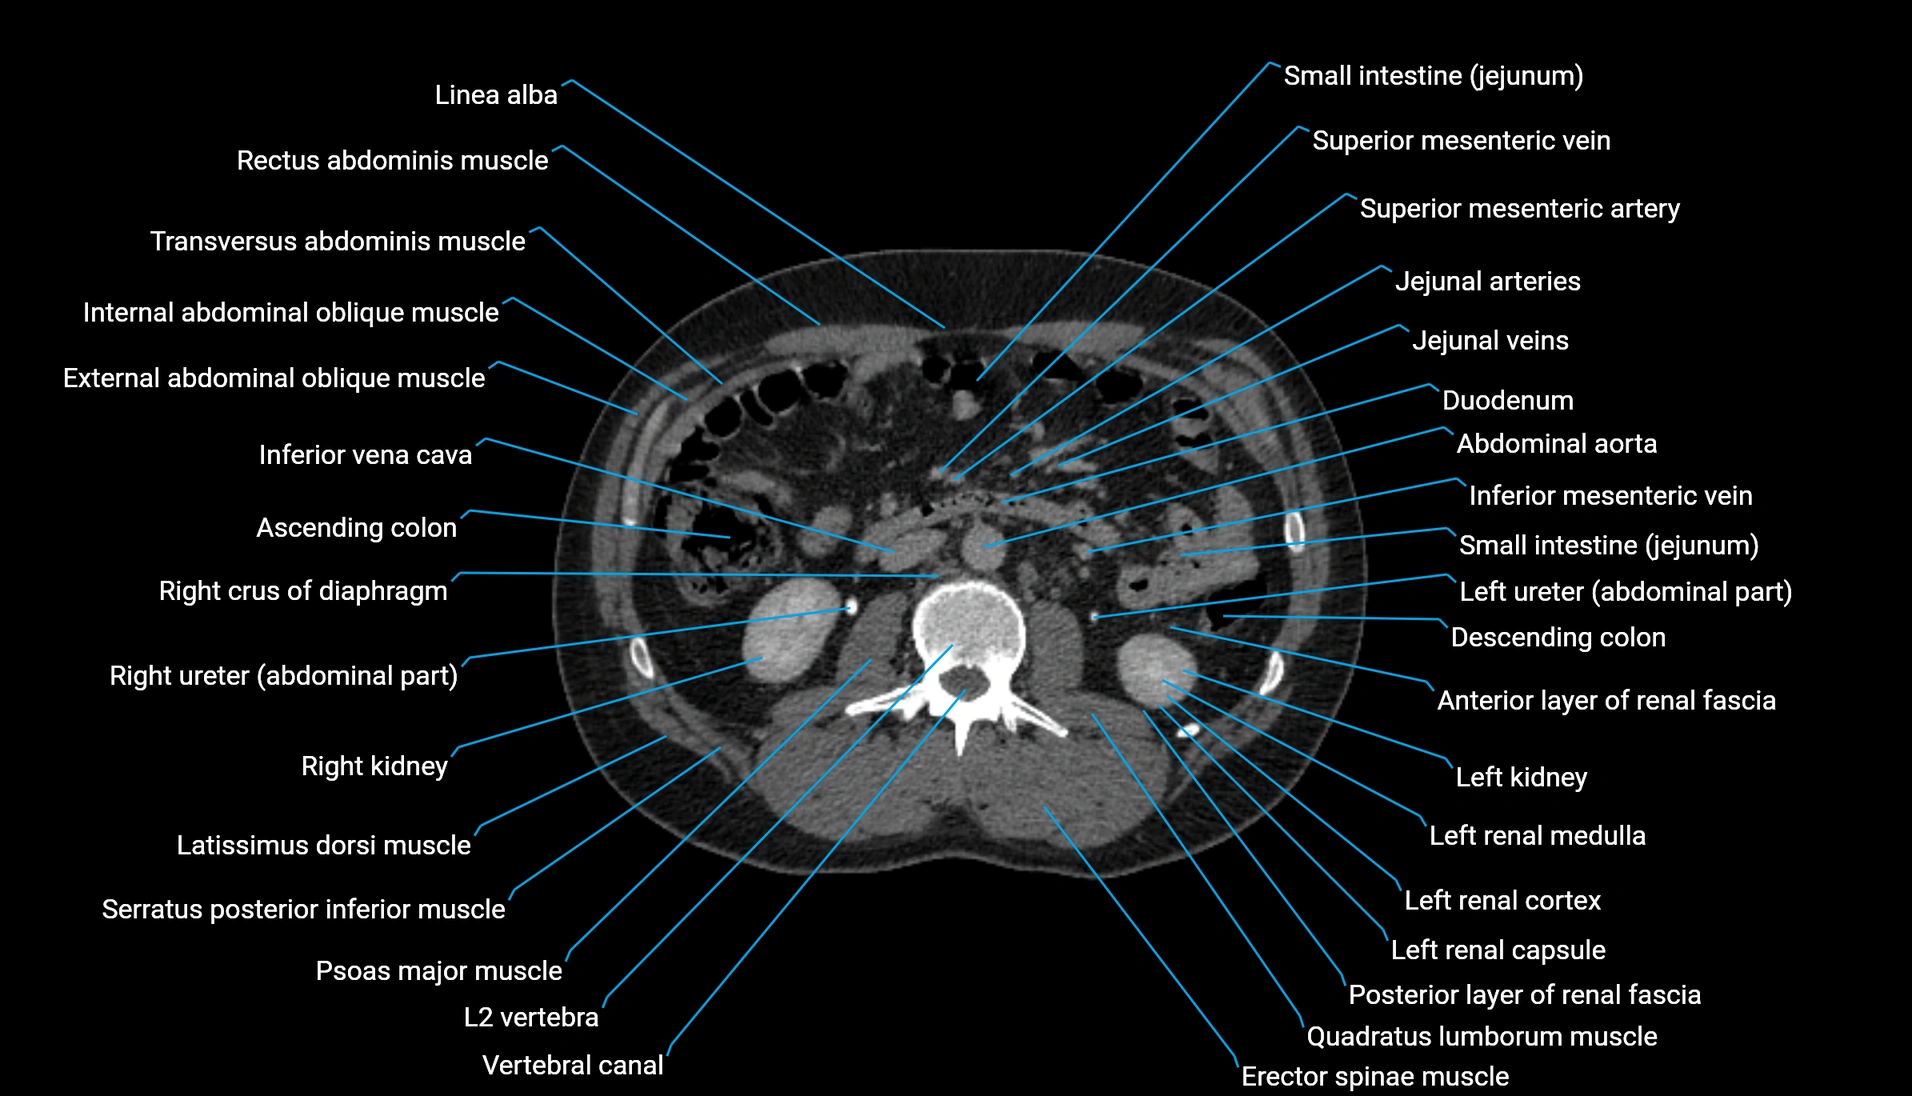

CT Appearance

Non-contrast CT:

-

Demonstrates cortical bone of acetabular rim in excellent detail

Detects fractures, dysplasia, retroversion, or bony overcoverage (pincer impingement)

3D reconstructions used in preoperative hip surgery planning

CT VRT 3D image

CT image